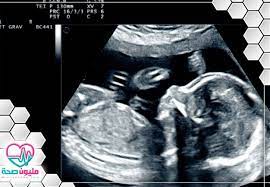

شكل الجنين في الشهر السادس بالسونار وأهم الفحوصات التي تتم في هذا الشهر مليون صحة